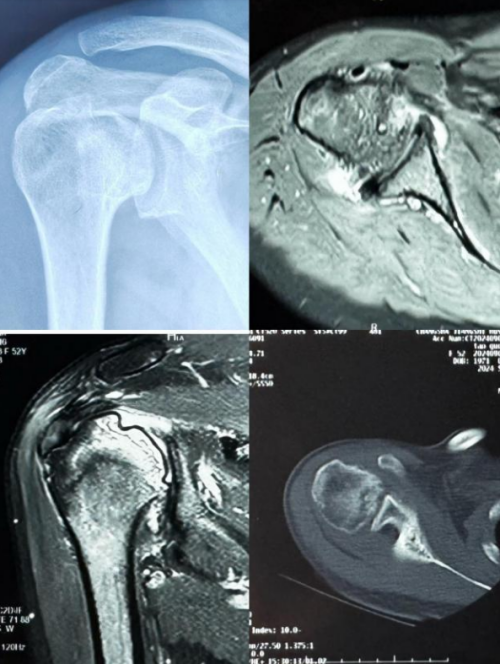

经人推荐,李阿姨慕名来到香港马会app 运动医学、创伤、关节、骨病科丑克主任专家门诊就诊,检查发现右三角肌、斜方肌、冈下肌、小圆肌萎缩,右侧肱骨头坏死,核磁共振检查显示肱骨头软骨下骨囊性变,肱骨头塌陷。丑克建议李阿姨行肩关节置换,随后入院治疗。

患者术前评估:右上肢无法正常上抬

术前影像检查显示肱骨头软骨下骨囊性变,肱骨头塌陷